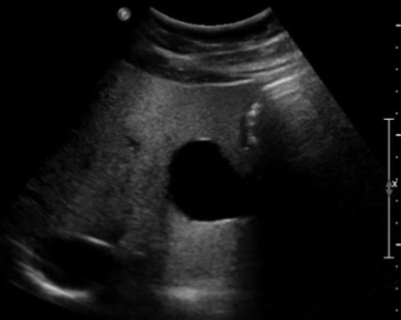

The image shows a hemangioma that causes a slower velocity and therefore makes a part of the diaphragm appear deeper than it really is